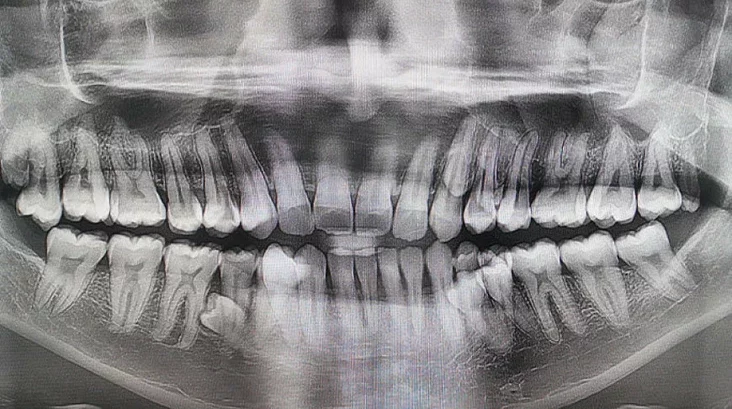

33‑гадовы жыхар Малайзіі Пратап Муніяндзі ўстанавіў незвычайны сусветны рэкорд: у яго ў роце 42 зубы, што на дзесяць больш, чым у сярэдняга чалавека, які звычайна мае 32. Гэты факт быў пацверджаны і занесены ў Кнігу рэкордаў Гінэса.

Сам мужчына доўгі час не падазраваў пра сваю асаблівасць. Пра гэта стала вядома ў 2021 годзе падчас сямейнай размовы, калі ён пажартаваў, што ў яго можа быць больш зубоў. Родныя налічылі 38, а пасля рэнтгенаўскага даследавання высветлілася, што яшчэ чатыры зубы не прарэзаліся. У пачатку 2023 года стаматолагі афіцыйна пацвердзілі, што ў яго ўсяго 42 зубы. Пры гэтым большасць з іх растуць роўна і не выклікаюць праблем.